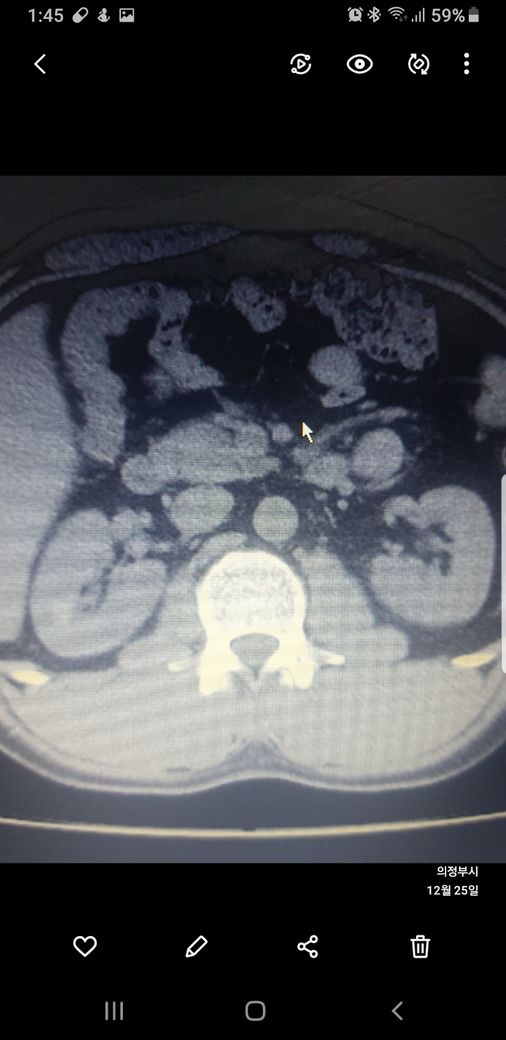

복부ct 작년 11월 , 올해 12월 촬영분입니다.

우측신장에 작년에는 1.7cm 물혹이 올해는 같은곳에 1.2cm 출혈성낭종이라는데

사진 1~4번째 는 작년

둘다 같은 병변이고 비조영증강에서 약간의 고음영 소견이 있어 출혈성 낭종이 의심됩니다.

신장의 낭성병변의 분류에서 1, 2, 2F, 3, 4이렇게 나뉘는데, 2에 해당되는 소견입니다.